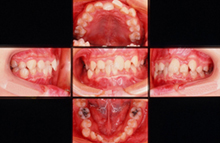

・CASE 1 ~ 乱ぐい歯 ~

治療前 13歳3ヶ月

治療後 13歳10ヶ月

CASE 1 ~乱ぐい歯~右中切歯の反対咬合と下顎の歯の凸凹を治したい。

治療前(初診時年齢)13歳3ヶ月の男児

前歯で噛み切りにくい

マルチブラケット装置(表側ワイヤー装着)永久歯を抜かずに治療しました

治療後 13歳10ヶ月 治療期間7ヶ月 治療費200,000円

副作用とリスク(歯の痛み、口内炎、しゃべりづらい、歯根吸収、歯肉退縮、後戻り、治療期間について説明しました。)